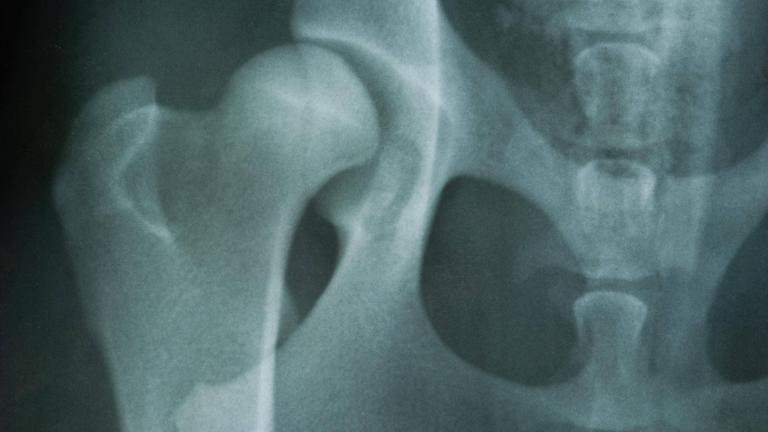

7. Röntgenbild einer Hüftgelenkdysplasie

Hüftgelenksdysplasie:Warum auch Erwachsene betroffen sind

von Corinna Klee